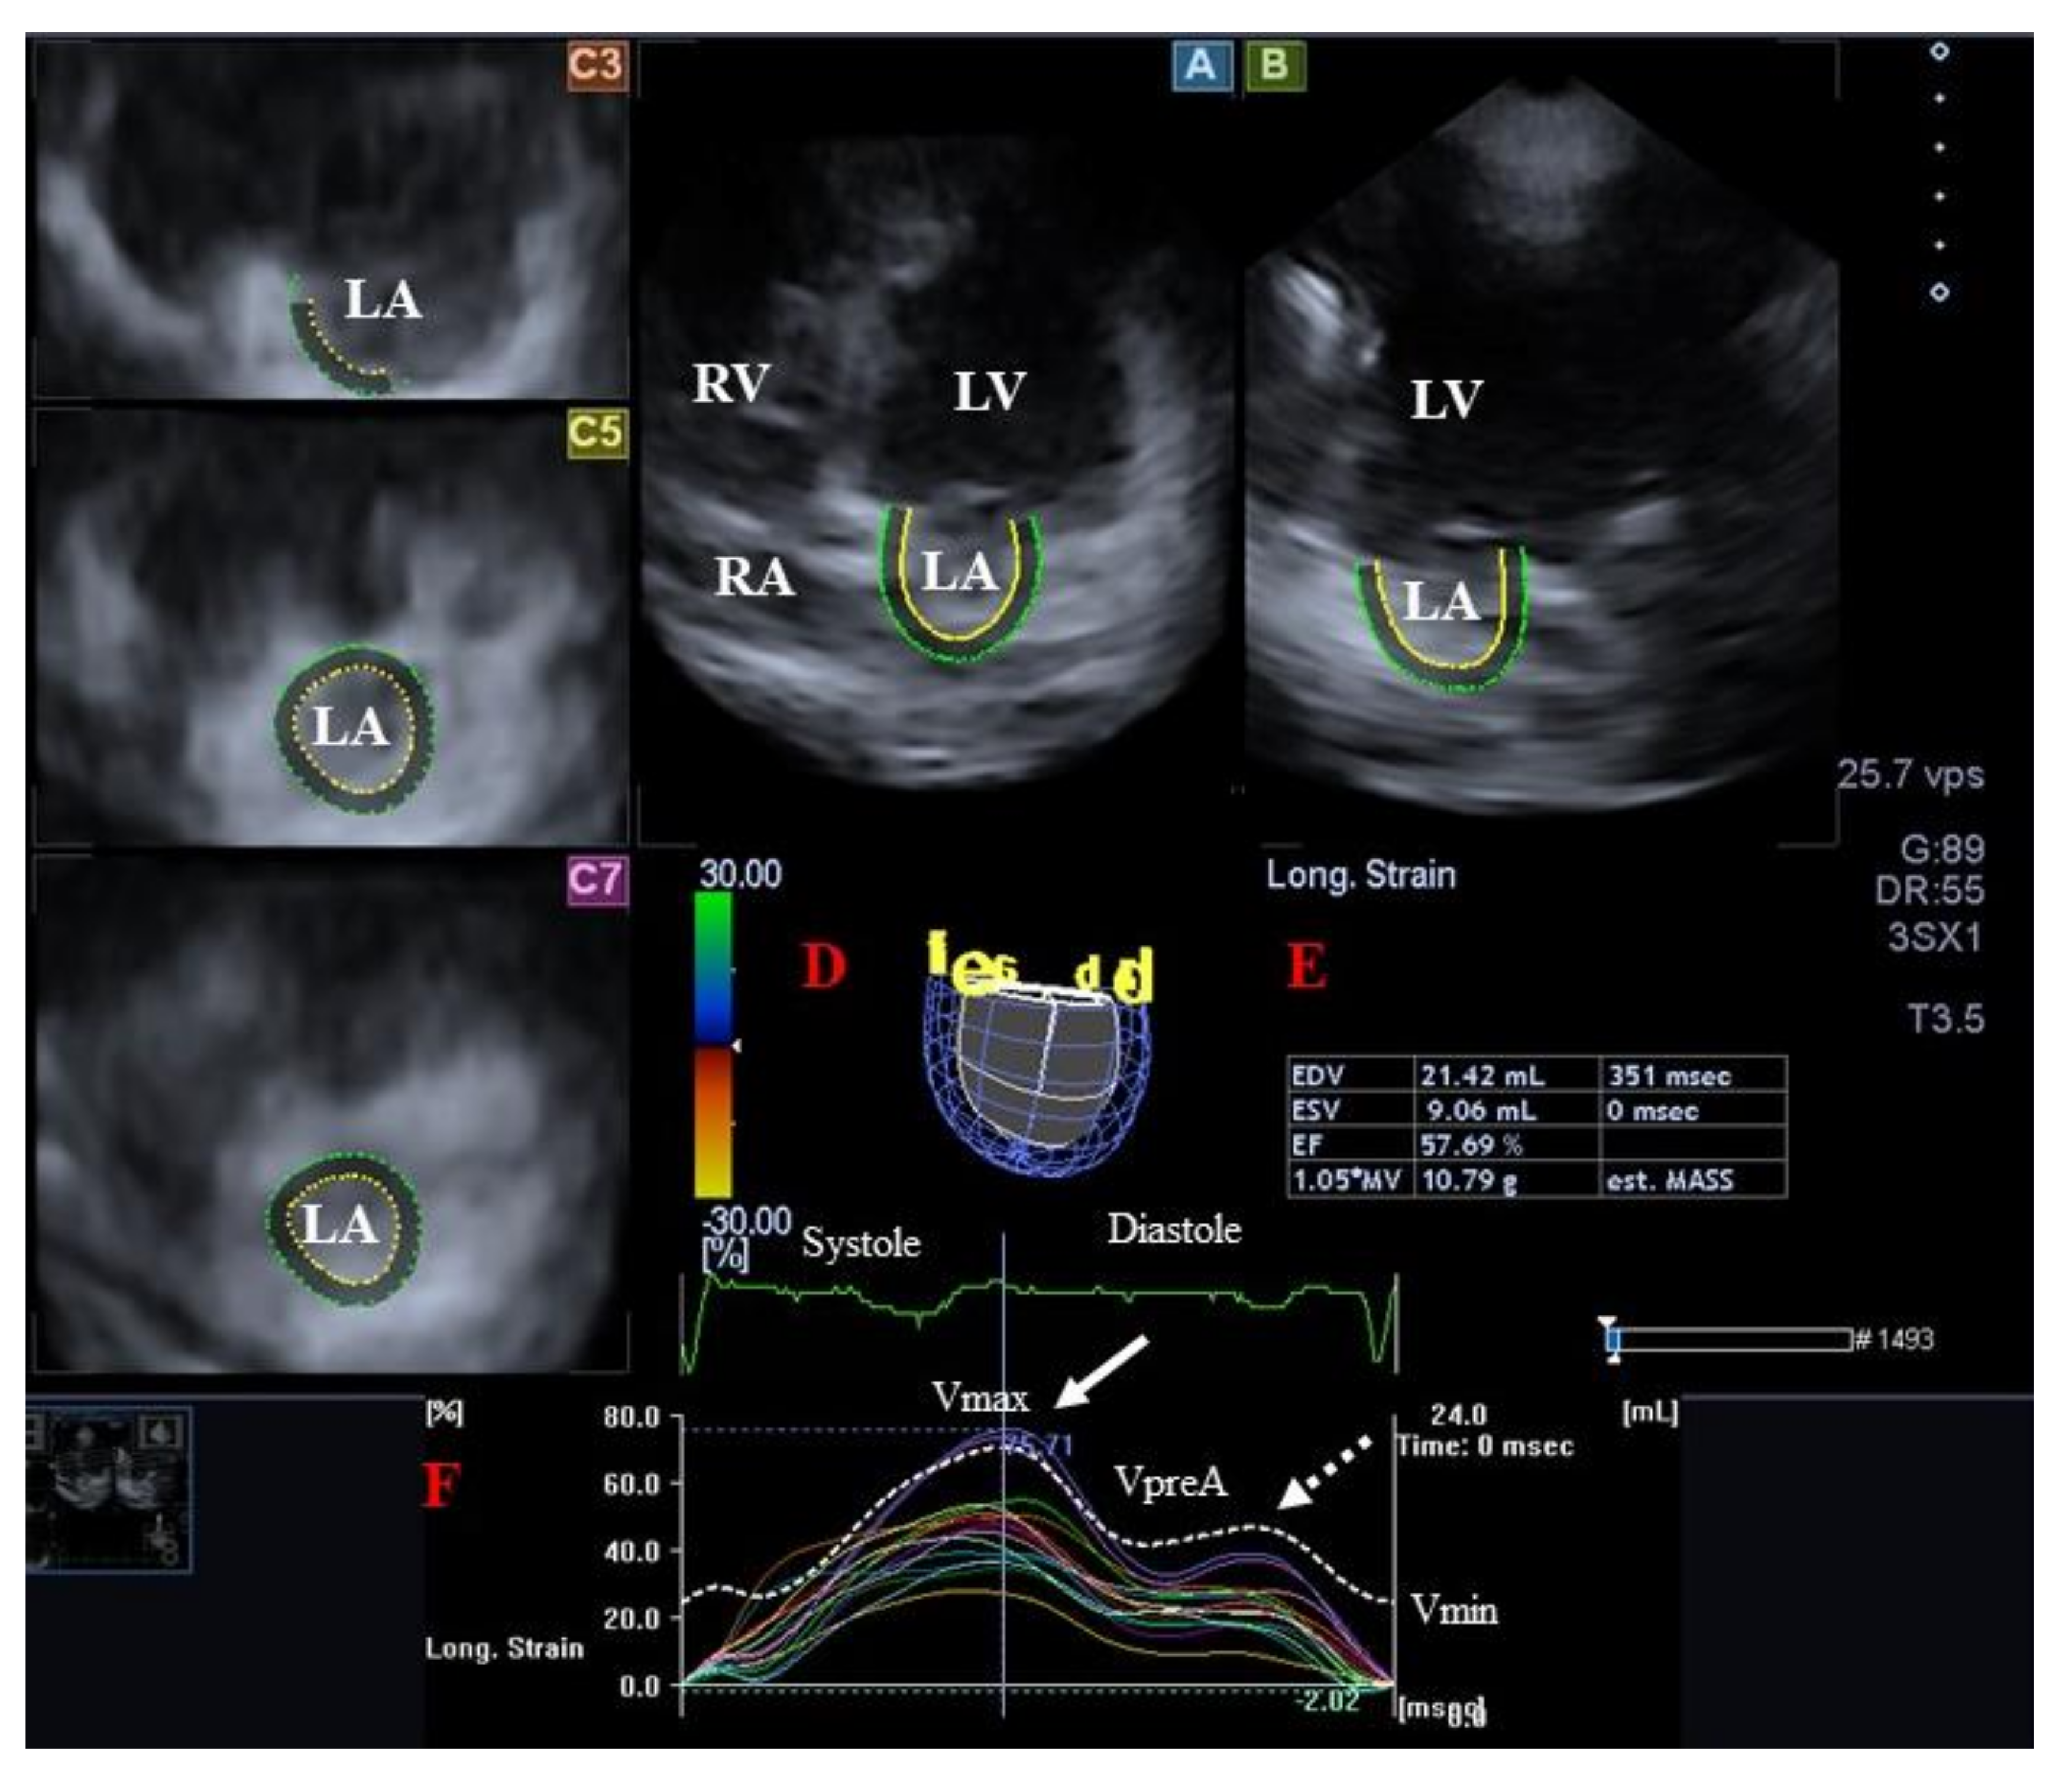

3.2. Left Atrium

3.2.1. Under Healthy Circumstances

3.2.2. In Acromegaly

- Kormányos, Á.; Domsik, P.; Kalapos, A.; Valkusz, Z.; Lengyel, C.; Forster, T.; Nemes, A. Three-dimensional speckle tracking echocardiography-derived left atrial deformation analysis in acromegaly (Results from the MAGYAR-Path Study). Echocardiography 2018, 35, 975–984. [Google Scholar] [CrossRef]